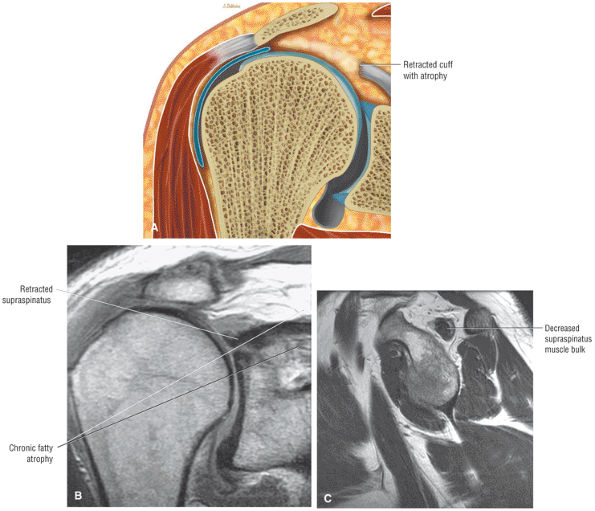

FIGURE 8.102 ● (A) The anterior undersurface of the acromion and the coracoacromial ligament form the coracoacromial arch. The subacromial subdeltoid bursa facilitates the passage of the rotator cuff and proximal humerus under the coracoacromial arch. (B) A superior axial image shows the anterior-to-posterior extent of the coracoacromial (CA) ligament perpendicular to the supraspinatus tendon. The fluid in the subacromial-subdeltoid bursa represents fluid between two serosal surfaces in contact with each other. One serosal surface is contributed by the undersurface of the coracoacromial arch and deltoid, and the other serosal surface is on the bursal side of the cuff.

|

![]() |

FIGURE 8.103 ● Pseudospur. The normal broad attachment of the coracoacromial ligament to the inferior surface of the acromion is shown on (A) T1-weighted coronal oblique and (B) sagittal oblique images. The low-signal-intensity acromial cortex (black arrows) and adjacent coracoacromial ligament and lateral slip of the deltoid attachment (white arrows) give the false impression of a small subacromial spur in the coronal plane. This pseudospur should not be misinterpreted as impingement; otherwise, unnecessary acromioplasties may be performed on patients with a normal coracoacromial ligament attachment and no associated acromial spurs.